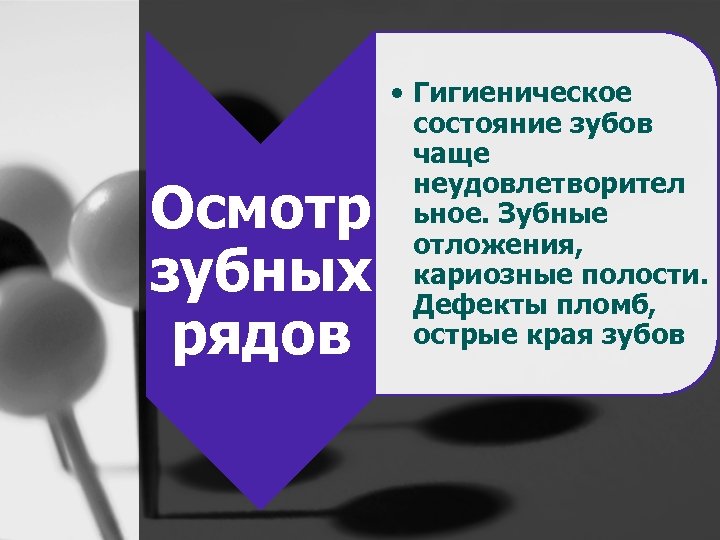

Осмотр зубных рядов • Гигиеническое состояние зубов чаще неудовлетворител ьное. Зубные отложения, кариозные полости. Дефекты пломб, острые края зубов